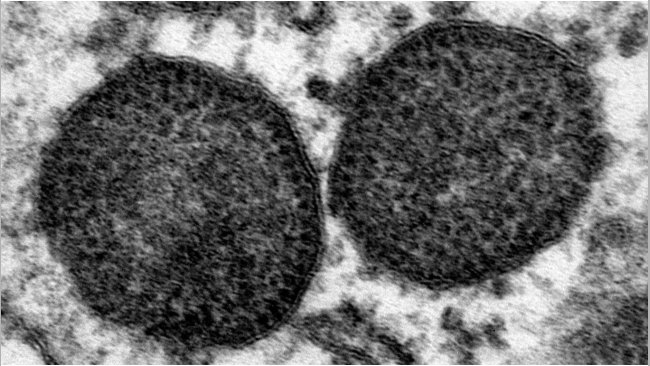

El circovirus porcino 2 (PCV-2) es una de las infecciones virales más frecuentes en cerdos, causando un impacto económico notable debido a los costos directos e indirectos de su control. Como otros virus ssDNA, el PCV-2 se caracteriza por una alta tasa de evolución, lo que lleva a la aparición de una gran cantidad de variantes con diferentes características biológicas y epidemiológicas. Con el tiempo, se han hecho varios intentos para organizar la heterogeneidad genética del PCV-2 en genotipos reconocidos. Esta categorización ha simplificado claramente las investigaciones epidemiológicas, permitiendo identificar diferentes patrones espaciales y temporales entre los genotipos. Además, también se ha planteado la hipótesis de la virulencia variable y la efectividad de la vacuna. Sin embargo, el rápido aumento en la actividad de secuenciación, junto con la alta variabilidad viral per se, ha desafiado la nomenclatura establecida previamente, conllevando a la definición de varios genotipos específicos de estudios e obstaculizando la capacidad de realizar estudios epidemiológicos comparables.